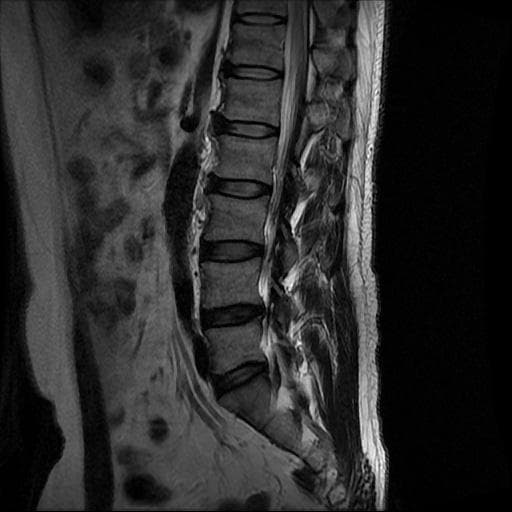

허리 MRI 디스크 상태 분석 부탁드립니다

건협에서는 관리해야 된다는데 디스크 협착이나 팽윤 등이 있는 상태인지 궁금합니다.

우선 현재로썬 사진만으론 판단을 하기에 제한이 되지만 사진상 디스크 상태는 심해보이지 않습니다.

요추부위의 하부 에서 약간의 팽윤이나 돌출로 의심해볼수 있는 정도이지만, 정확한 상태는 관련 전문의에게 진료시 문의를 하시는 것을 추천드립니다.